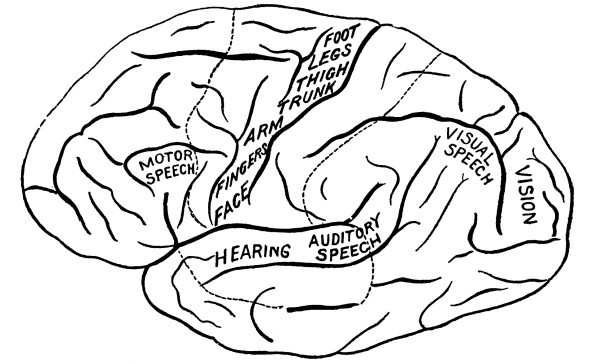

The Cerebrum, 75—The Cerebellum, 78—Pons Variolii, 78—Medulla Oblongata, 78—Spinal Cord, 79—Brain-centers, 81—Motor Tract, 82—Sensory Tract, 82—Reflex Action, 83—Cranial Nerves, 83—Spinal Nerves, 84—Brachial Plexus, 85—Sacral Plexus, 85—The Sympathetic System, 87—The Sympathetic Nerves, 87. |

| The Nervous System | 75 |